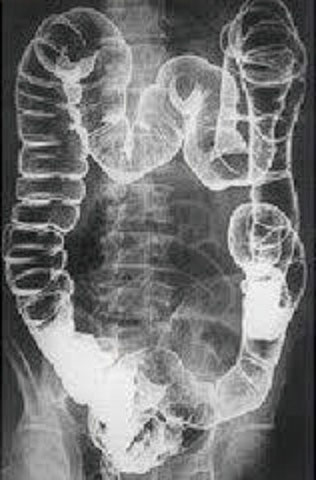

X線を用いて、人体の内部構造を画像として記録します。非侵襲的で短時間の検査が可能なのが特徴です。主な検査部位は胸部、腹部、骨、脊椎になります。